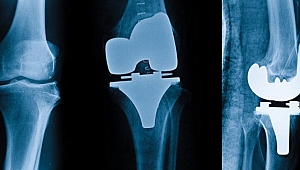

Diz protezi ömürlük bir ameliyat mıdır?